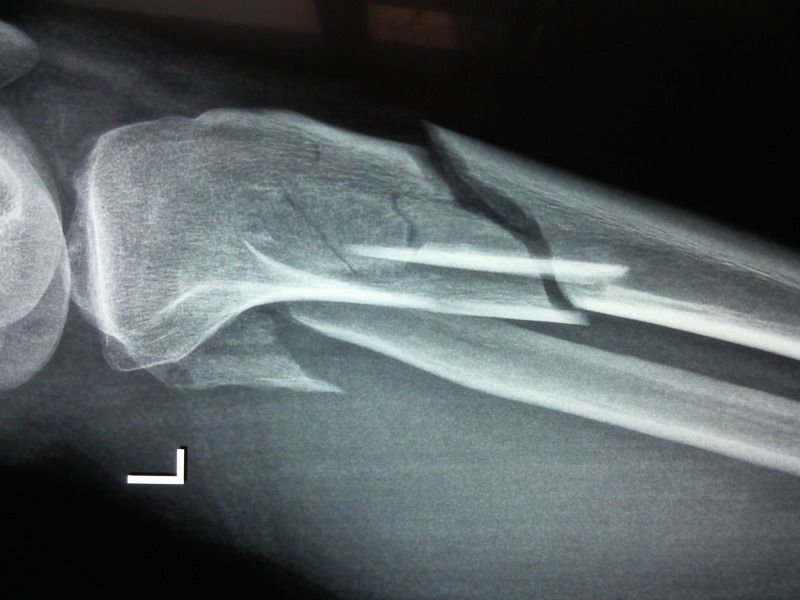

沭阳交通医院联合专家组完美完成一例股骨远端合并胫骨平台粉碎性骨折手术 雪花新闻 | 沭阳交通医院联合专家组完美完成一例股骨远端合并胫骨平台粉碎性骨折手术 雪花新闻 | 沭阳交通医院联合专家组完美完成一例股骨远端合并胫骨平台粉碎性骨折手术 雪花新闻 |

脛骨天蓋骨折 足関節の機能障害を防ぐためにも正確な整復が必要となります。 このため、偏位がまったくない軽微な骨折であればギプス固定などの保存的治療を行いますが、多くはネジやプレートを使用して偏位部を整復し固定する手術が必要となります。 また、粉砕が激しく、正確に整復できない場合には、欠損部分に自分の腸骨の一部や人工骨を移植することもあります。 強固に脛骨骨折高原骨折の場合、 手術療法 が適応となるのは、 以下のような場合であると言われています。 ・転位型である ・脛骨関節面が5mm以上の陥没している 加えて、年齢や生活スタイル、体力や既往歴などから総合的に判断して、 手術療法の適応となります。 代表的な手術療法の方法としては、 ・Bookopen法(関節切開法) ・関節鏡視下法 があります。 Bookopen法(関節切開法) Book